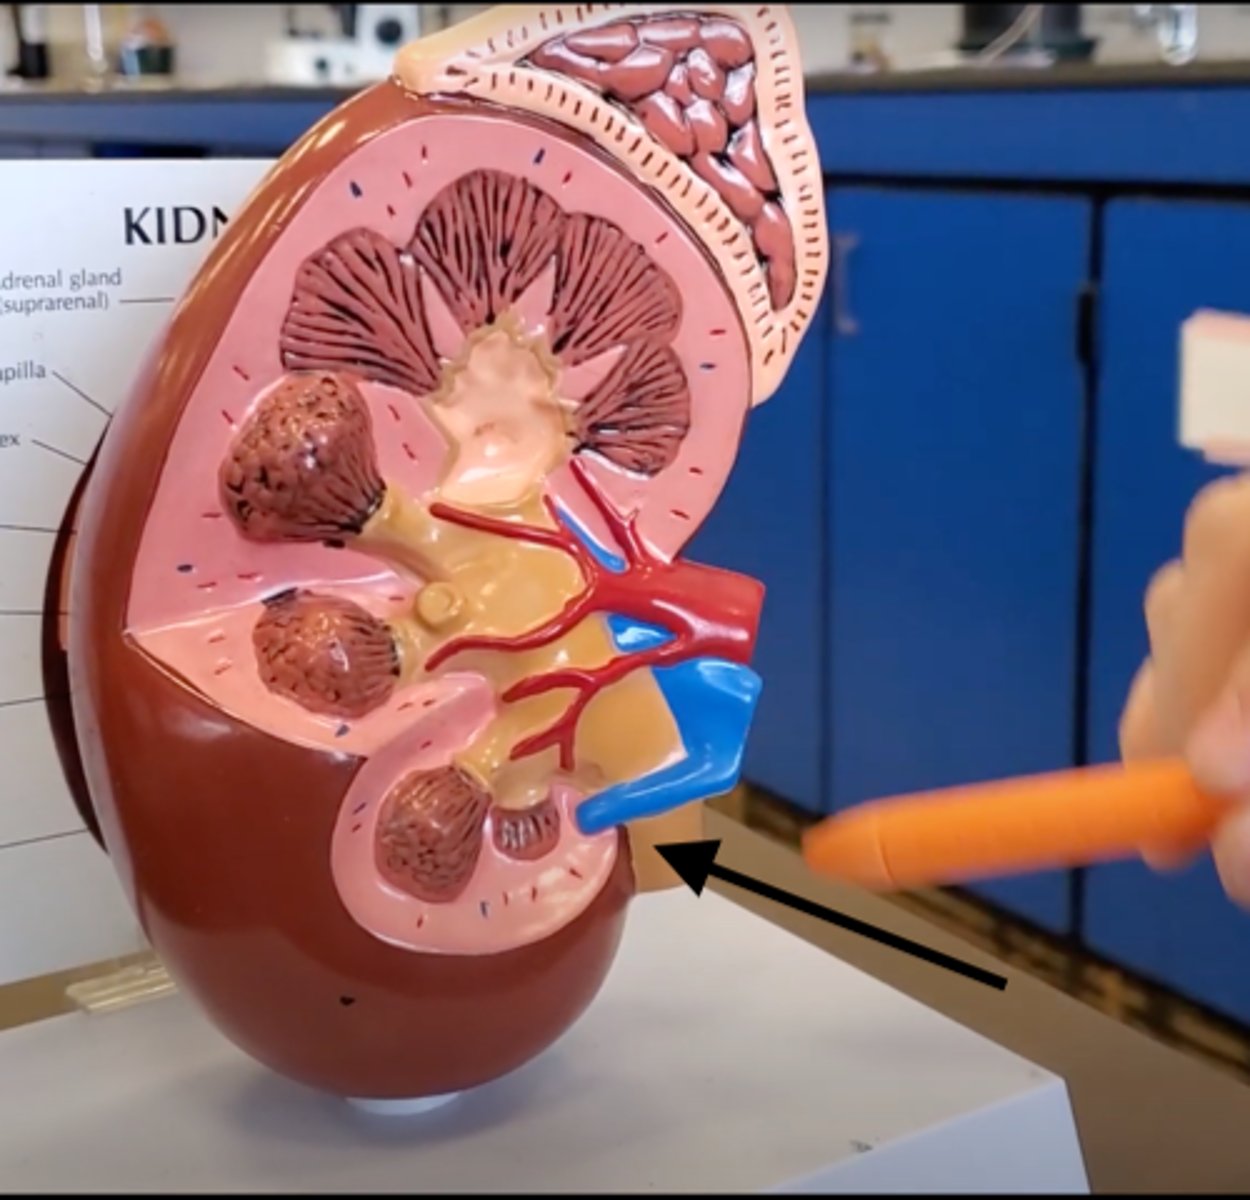

renal pyramid

2

renal column

3

cortex

outer layer of the kidney

ureter

A duct leading from the kidney to the urinary bladder.

nephron

the functional unit of the kidney

Adrenal gland

A pair of endocrine glands that sit just above the kidneys and secrete hormones that help arouse the body in times of stress.